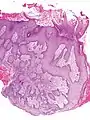

- Pseudoepitheliomatous hyperplasia (PEH) is a benign condition characterized by hyperplasia of the epidermis and epithelium of skin appendages,[31] with irregular squamous strands extending down into the dermis,[32] and closely simulating squamous cell carcinoma (SCC).[31]

Pseudoepitheliomatous hyperplasia (PEH), low magnification, with acanthotic squamous epithelium with irregular thick finger-like downgrowths into the underlying dermis.